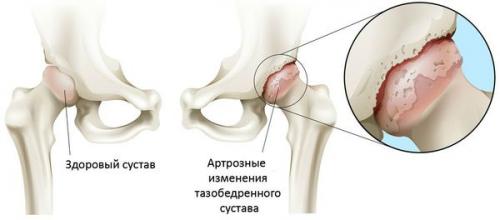

Тазобедренный сустав образован двумя костями: подвздошной и бедренной. Головка бедра сочленяется с вертлужной впадиной подвздошной кости, образуя своеобразный «шарнир». При движениях вертлужная впадина остается неподвижной, а головка бедренной кости двигается в различных направлениях, обеспечивая сгибание, разгибание, отведение, приведение и вращательные движения бедра.

Во время движений суставные поверхности костей беспрепятственно скользят друг относительно друга, благодаря гладкому, упругому и прочному гиалиновому хрящу, покрывающему полость вертлужной впадины и головку бедра. Кроме того, гиалиновый хрящ выполняет амортизирующую функцию и участвует в перераспределении нагрузки при движениях и ходьбе.

В полости сустава находится небольшое количество суставной жидкости, которая играет роль смазки и обеспечивает питание гиалинового хряща. Сустав окружен плотной и прочной капсулой. Над капсулой находятся крупные бедренные и ягодичные мышцы, которые обеспечивают движения в суставе и, наряду с гиалиновым хрящом, также являются амортизаторами, предохраняющими сустав от травм при неудачных движениях.

При коксартрозе суставная жидкость становится более густой и вязкой. Поверхность гиалинового хряща высыхает, теряет гладкость, покрывается трещинами. Из-за возникшей шероховатости хрящи при движениях постоянно травмируются друг о друга, что вызывает их истончение и усугубляет патологические изменения в суставе. По мере прогрессирования коксартроза кости начинают деформироваться, «приспосабливаясь» к увеличившемуся давлению. Обмен веществ в области сустава ухудшается. На поздних стадиях коксартроза наблюдается выраженная атрофия мышц больной конечности.

Артроз тазобедренного сустава (коксартроз) — это хроническое дегенеративное заболевание сустава, которое ведёт к деформации костной ткани. При коксартрозе в патологический процесс вовлекаются все компоненты сустава: суставные хрящи, костные структуры, прилегающие к хрящам, синовиальная оболочка, связки, капсула и прилегающие к суставу мышцы. При заболевании разрушается суставной хрящ, появляются микропереломы костей и остеофиты (костные разрастания), возникает воспаление мышечно-связочного аппарата тазобедренного сустава.